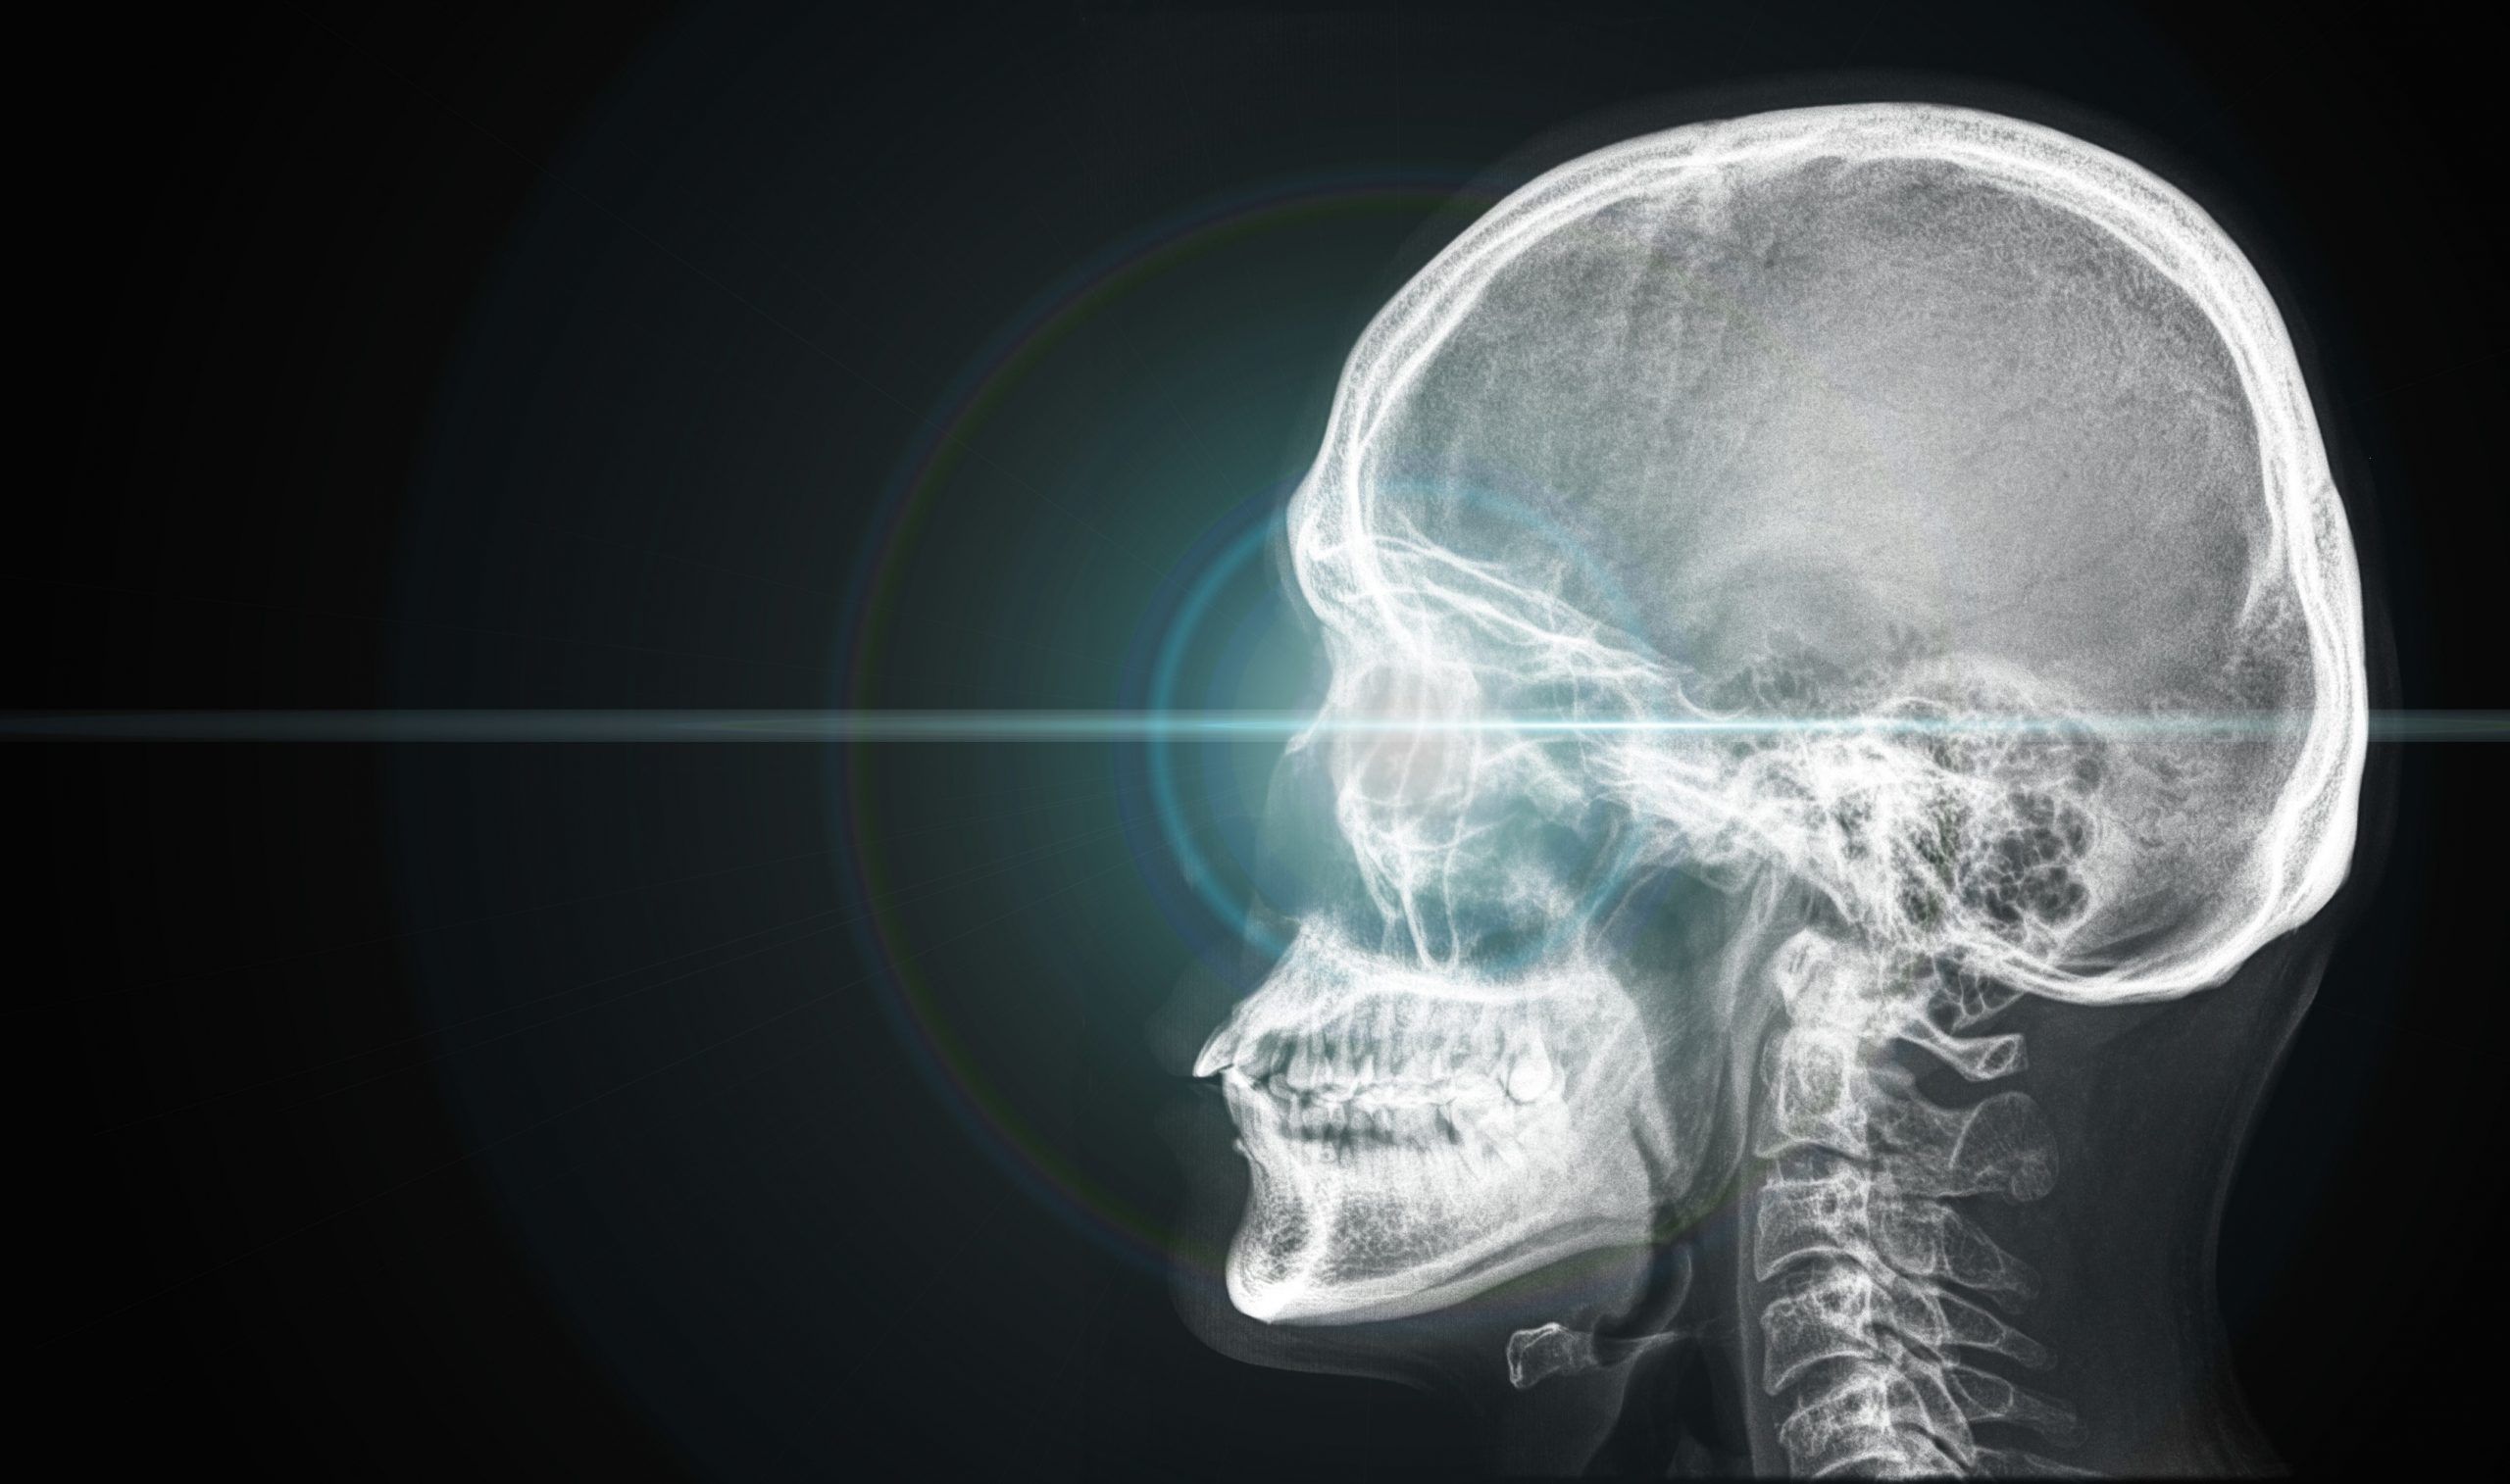

The Hidden Effects of Head Injuries

Just as concerning is the hidden tragedy that every head injury can damage the neck. Since the primary focus at the time of a head injury is the head, the neck is very often overlooked. There are distinct signs of neck injuries, vertebral subluxations as an example, that can be found during an examination at the time of injury, as well as days, weeks, months and even years later. Due to the focus and pressure rising on concussions, the rapid forward-backward motion commonly known as whiplash has been swept under the rug. It is downplayed and often ignored. And yet, the vast majority of head injuries also have the mechanism to cause whiplash injuries as well.

Most neck injuries that occur in conjunction with head trauma are not severe enough to cause paralysis, but can cause pressure on nerves that affect the health of the victim on many levels. Whiplash and concussion have serious long-term effects, including depression, memory loss, fatigue, mood swings, headaches and chronic instability. Head and neck injuries also damage sensitive nerves in these regions as they exit the spine. Damage to ligaments can mean continual nerve irritation and interference if proper care is not given. The effects from these injuries can last decades after the pain goes away.